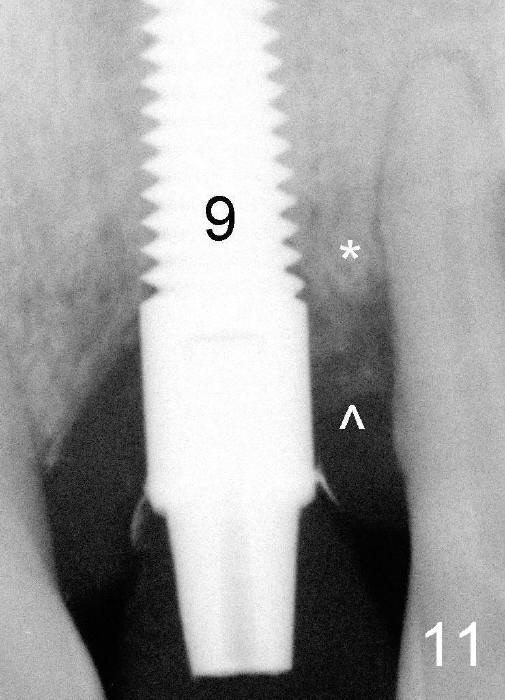

Fig.11: Six months postop. The crest bone (*) and the bone graft (^) appear to have been fused.